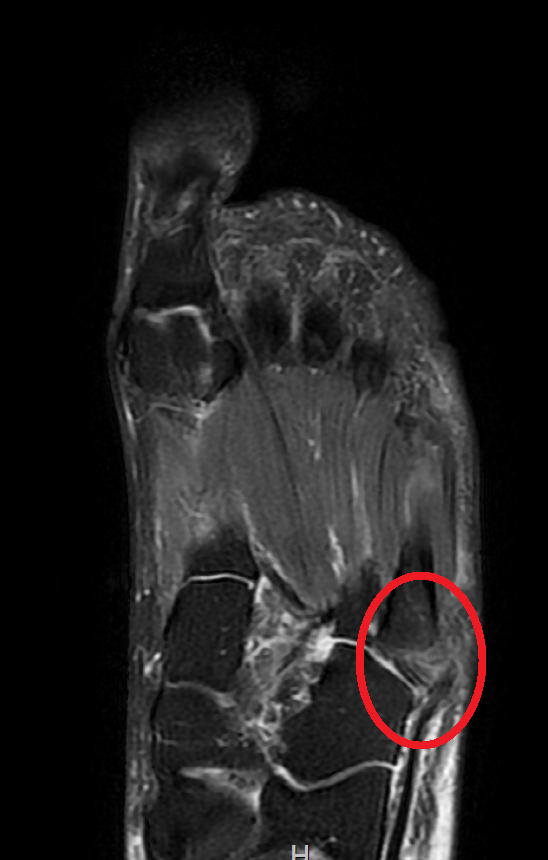

환자분의 MRI입니다.

MRI 상에서 빨간 동그라미 안에 골절은 보이지만 옆에 붙어 있는 힘줄의 손상은 없기 때문에 힘줄 수술까지는 필요 없어 보입니다. 불행 중 다행입니다.